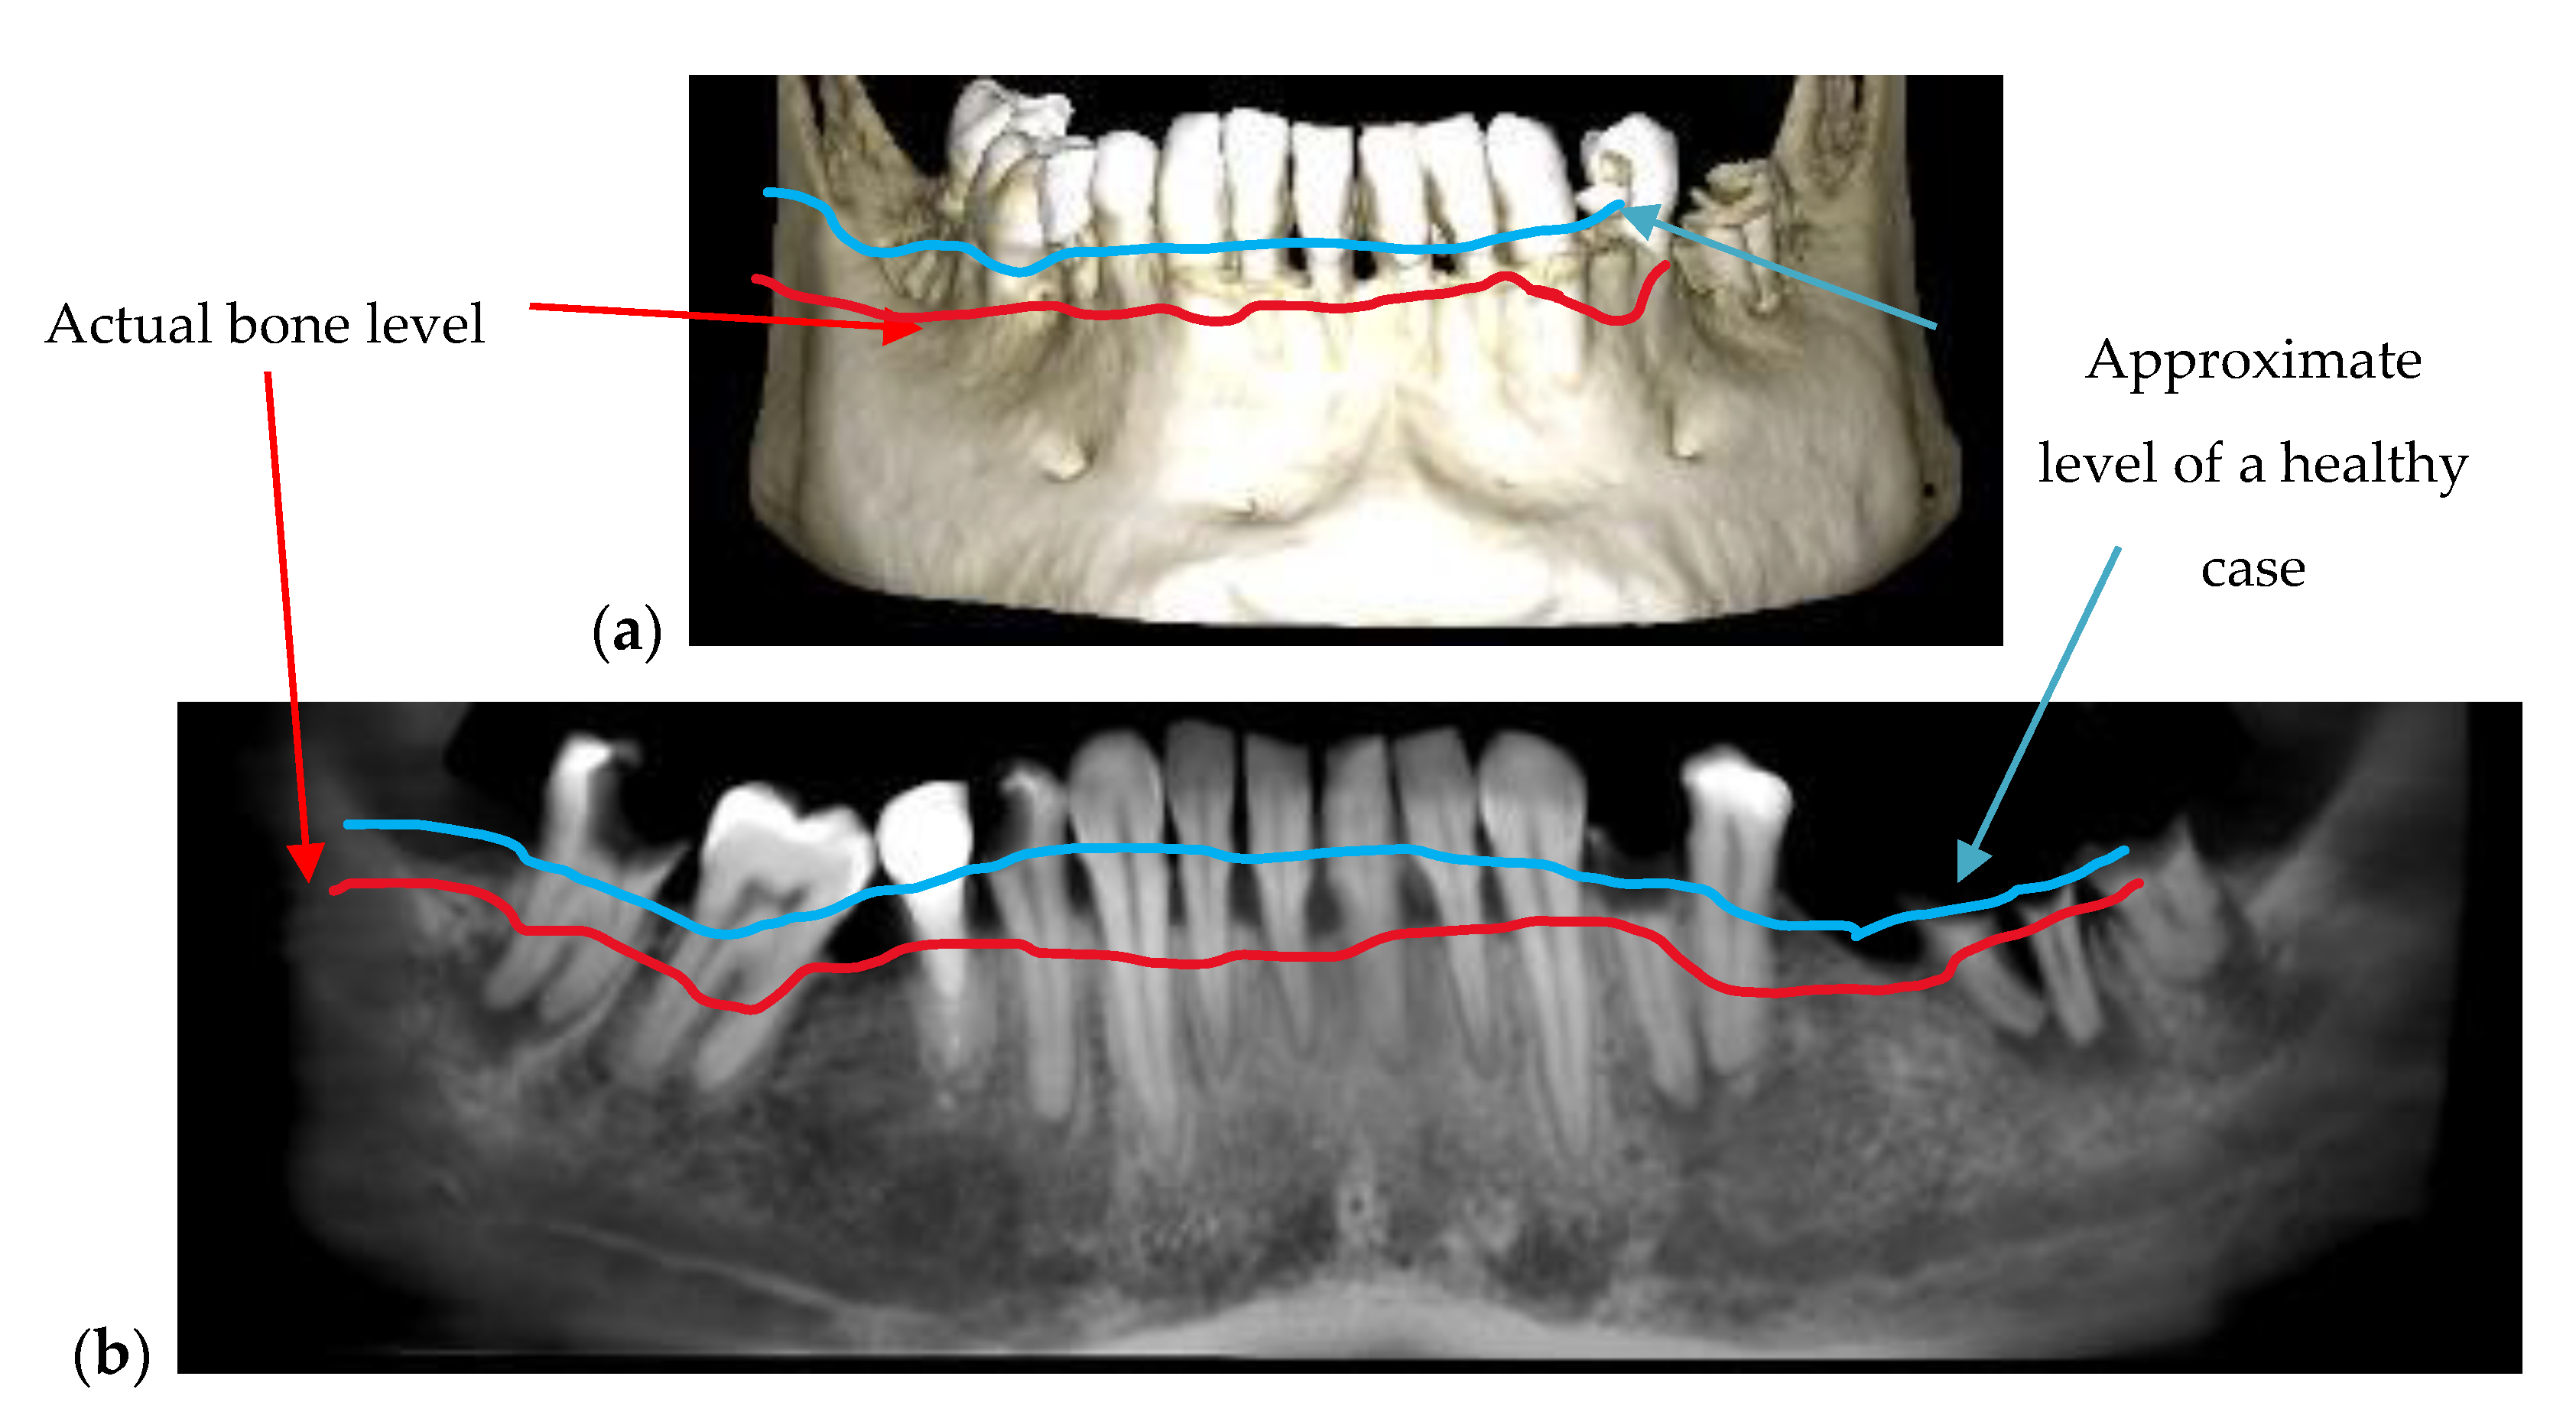

| Periodontitis | The disease can be monitored during the treatment (example, Figure 5) | Exact measurements of bone loss/gain are possible |